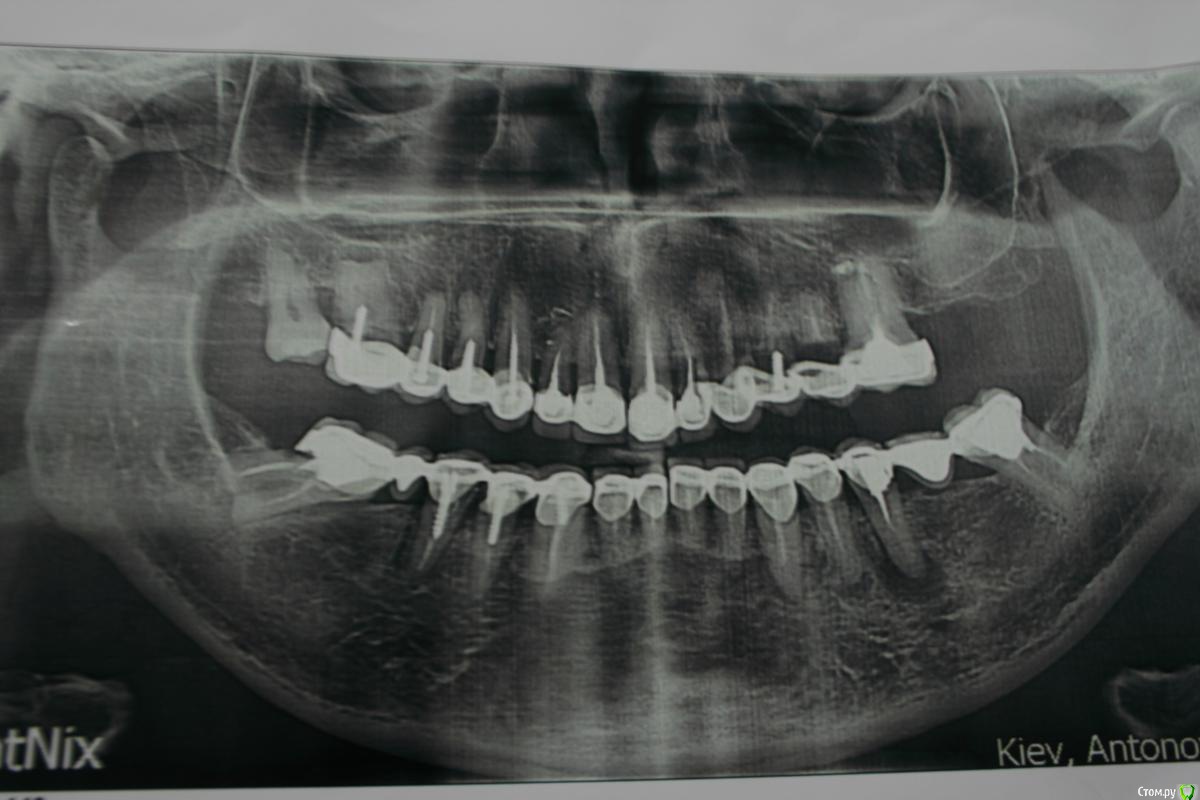

DmitrySH Опубликовано 22 декабря, 2015 Поделиться Опубликовано 22 декабря, 2015 Да уж, работы полон рот. И не только 47 будет удален. 2 Ссылка на комментарий

St. Опубликовано 22 декабря, 2015 Автор Поделиться Опубликовано 22 декабря, 2015 (изменено) Да, Вы правы. Вот такая вот подготовка под мк. Со слов лет 15 простояло. Будем спасать, что можно. Изменено 22 декабря, 2015 пользователем St. Ссылка на комментарий

Гарриевич Опубликовано 23 декабря, 2015 Поделиться Опубликовано 23 декабря, 2015 ОПТГ трындецхотя у меня щас случай по жестче есть, в Белоруссии поналечили по туризму Ссылка на комментарий